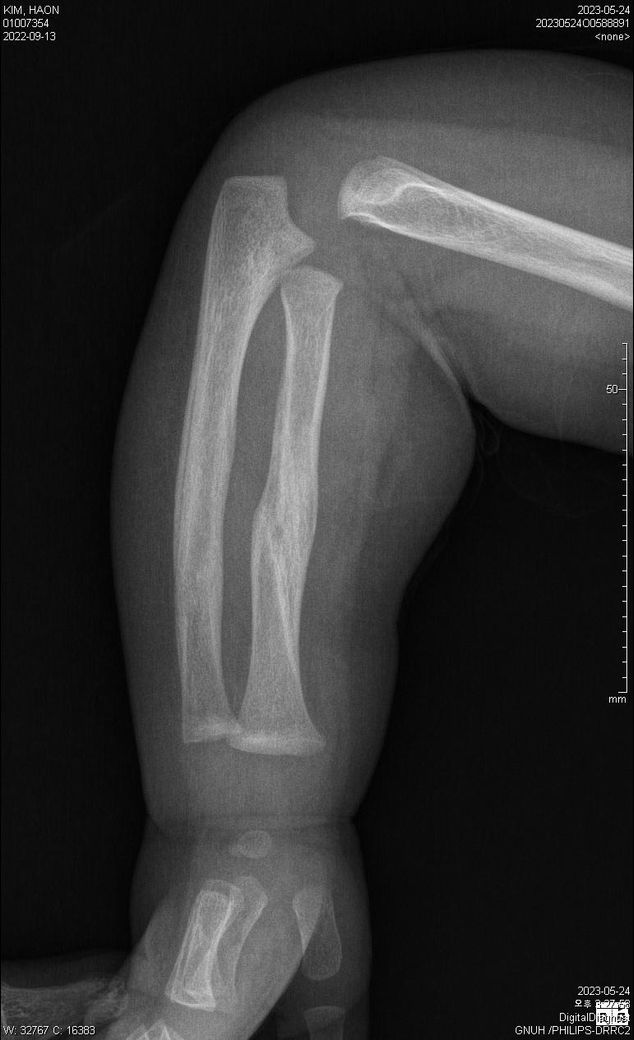

첨부된 파일에 기재된 사실과 같이 23년 5월 24일 촬영된 양팔 X선 2장과

23년 7월 11일 촬영된 양팔 X선 2장입니다.

양팔이 골절이 되었었는데요,

1) 5월 24일 X선이 가골형성 시기인지, 재형성(리모델링) 시기인지 궁금합니다.

3) 5월 24일 X선에 비해 7월 11일 X선은 또한 어떤 치료단계인지 문의드리고자 합니다.

4) 종합하자면 3월 초~ 중순에 골절이 일어났다고 보는게 타당한지?

• 1번 째 사진